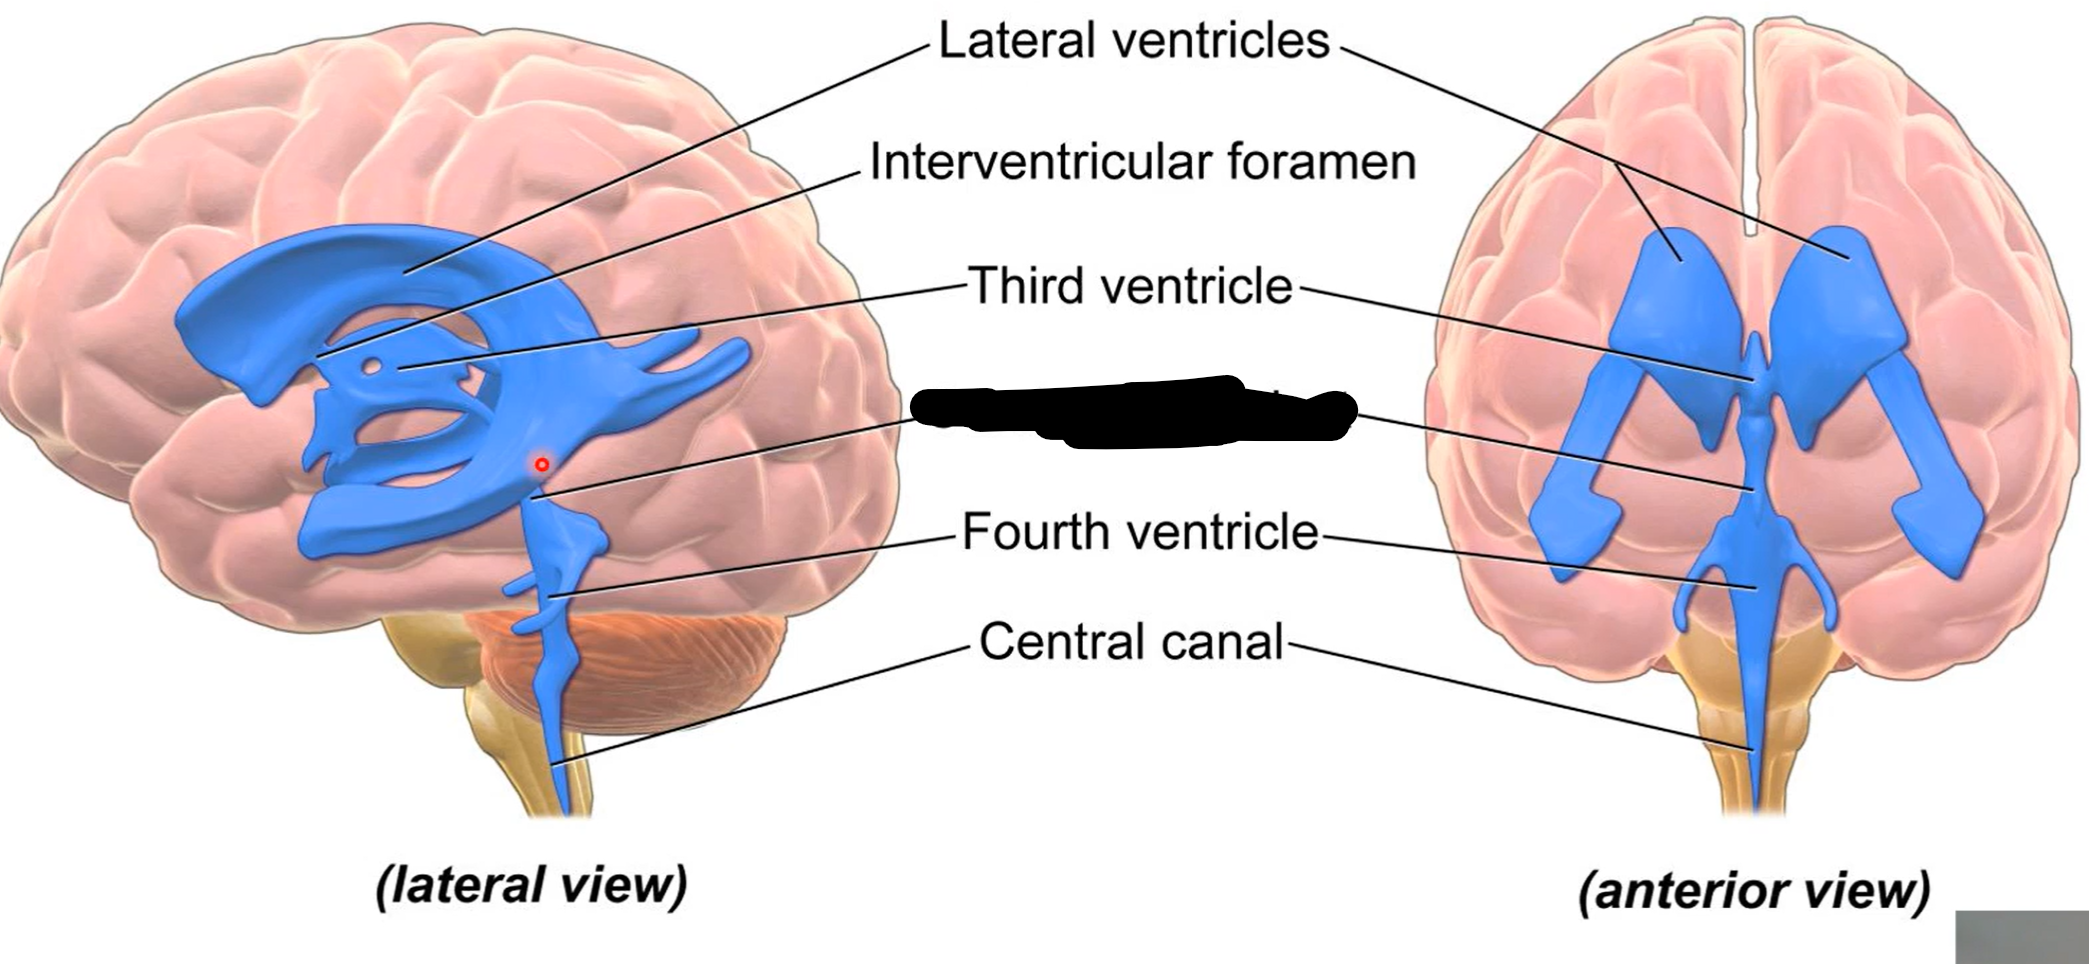

What do brain ventricles contain?

CSF

What makes CSF?

Choroid plexus

Where does CSF go from ventricles?

Subarachnoid space to enter circulation via arachnoid granulations

Choroid plexus

What carries CSF from 4th ventricle to subarachnoid space?

Median and lateral apertures

Arachnoid granulations

Lateral ventricles

Interventricular foramen

Third ventricle

Cerebral aqueduct

Fourth ventricle

Central canal